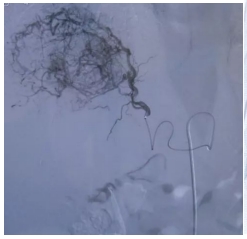

▲圖1 許榮德教授帶領我院腫瘤血液介入團隊開展肝動脈灌注化療術+胰十二指腸上動脈灌注化療術

許榮德教授介紹:手術過程全程清醒,不開刀,只需經(jīng)股動脈予一細針行股動脈穿刺就可建立介入通道,然后在DSA設備引導下行血管造影顯示腫瘤位置、大小及血供等情況,通過供應腫瘤的靶血管把化療藥物注入腫瘤內(nèi),可顯著提高腫瘤局部的藥物濃度,在提高治療效果的同時減輕藥物對全身的毒副作用。

圖2、圖3 經(jīng)肝動脈造影,顯示腫瘤供養(yǎng)血管,精確超選靶血管進行治療。